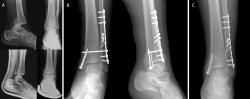

• Traslación peronea (Cotton test) (Figura 1).

Figura 1. A: squeeze test; B: test de rotación externa.